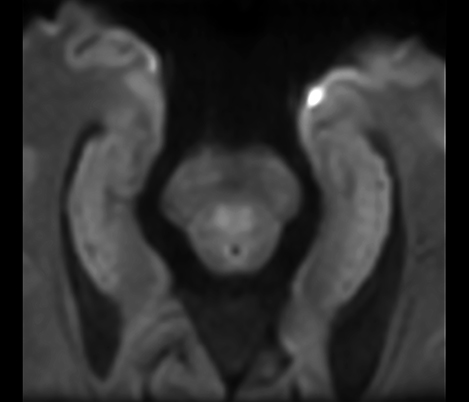

Klinische Fallbeispiele für nahezu jede anatomische Struktur Sehen Sie sich mehr als 100 klinische Fallbeispiele von Kollegen auf der ganzen Welt an, die zeigen, wie die digitale MR-Technologie von Philips Ihre Anforderungen in der Bildverarbeitung unterstützt.